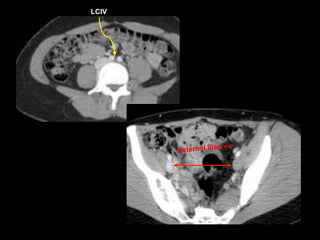

41 YO F, May - Thurner

Lack of Augmentation – suspect upstream obstruction

LCIV

External iliac vv.

41 YO F,May - Thurner Lack of Augmentation – suspect upstream obstruction

• 87.

• 89.

• 90.

Indirect Dx byarterial CTA

• 91.

• 120 cccontrast • Monitoring delay = 40sec • Smart prep at infrarenal IVC 28F May-Thurner syndrome, CIV/EIV stent placement 3 years ago Courtesy of Anne Chin, MD F/U stenting for May Thurner